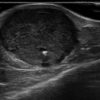

U máu

» Thông tin: Nam giới – 66 tuổi.

» Lâm sàng: Sưng cẳng chân.